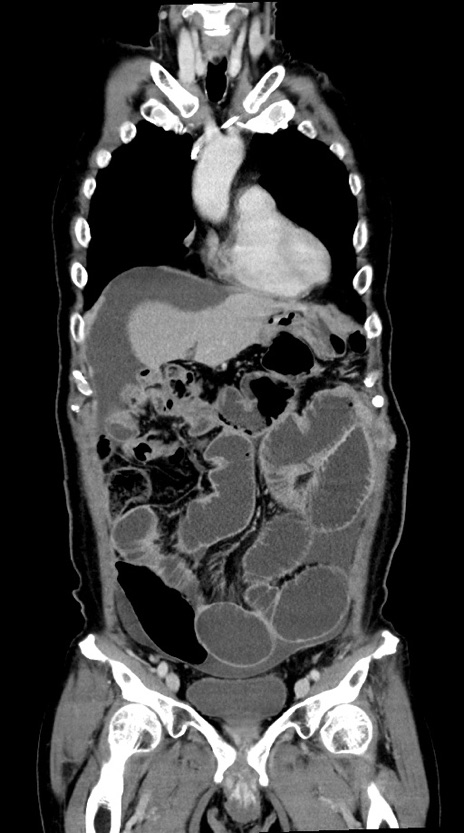

症例28(冠状断像)

【症例】60歳代男性

【主訴】嘔吐

【現病歴】胃癌にて胃全摘後。食思不振が悪化し、夜中に嘔吐することがある。

【既往歴】胃癌、胃全摘、脾摘、胆摘後

【データ】WBC 5900、CRP 10.56